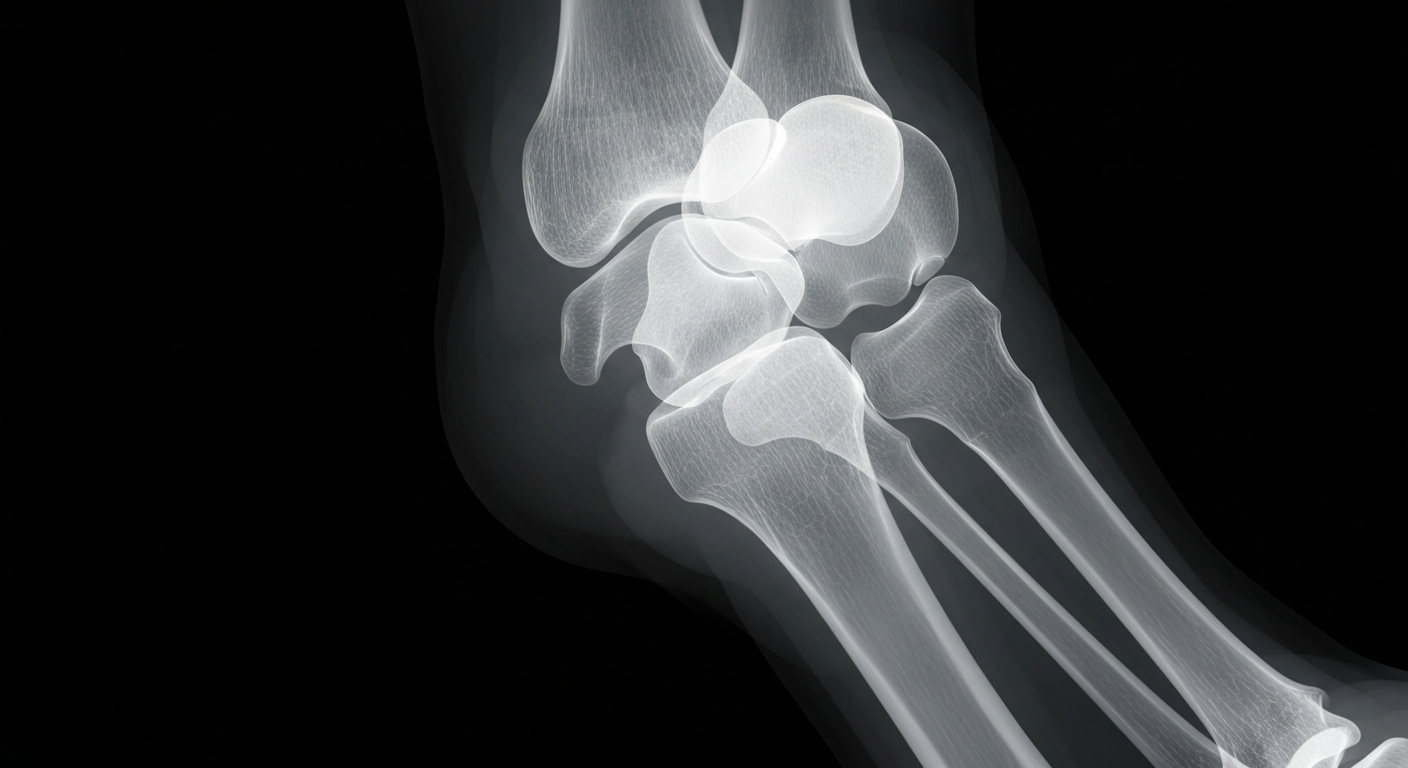

Knowing when to get an X-ray for a sprained ankle can prevent long-term complications.

An X-ray examination can help determine if a twisted ankle is a sprain or a fracture, ensuring proper treatment and preventing long-term complications.Idaho Falls TodayMost twisted ankles don't require an X-ray, but some do - and waiting too long to find out can lead to a longer, more complicated recovery. Fractures need different treatment than sprains, and if not treated correctly, can cause chronic pain, instability, and arthritis later on. Doctors recommend getting an X-ray the same day if there is severe pain, rapid swelling, deformity, or trouble walking, as these could be signs of a fracture rather than just a sprain.

Knowing when to get an X-ray for a twisted or sprained ankle is important because a fracture requires different treatment than a sprain. If a fracture isn't treated properly, it can lead to long-term issues like chronic pain, instability, and arthritis. Getting checked out right away can help ensure the injury is properly diagnosed and treated.

A sprain is a stretched or torn ligament, while a fracture is a broken bone. Early on, they can feel similar, but fractures need different treatment. Some fractures are small and stable, while others may shift out of place or involve the joint, requiring a boot, cast, or surgery. If a fracture isn't treated correctly, the bone can heal in the wrong position, leading to long-term problems.